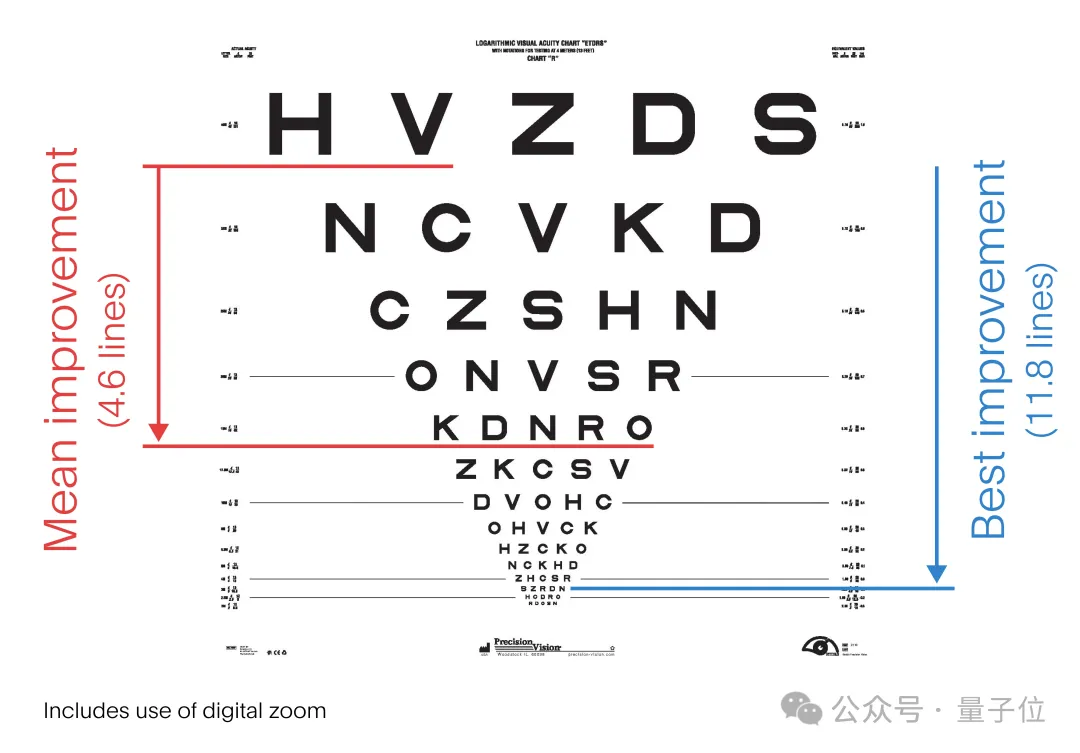

结果表明,患者使用PRIMA时,视力得到了显著的提高,阅读一系列字母时敏锐度明显增加,有些人甚至可以阅读更长的文字。

在经典的视力表中,患者开始时的平均视力为 20/450(正常视力被认为是20/20,在美国20/200或更差被定义为失明)。

一年后,32名受试者平均能够多阅读视力表上的近5行,即23个字母,也就是平均视力提高到了20/160。

如果使用植入物的内置变焦和放大功能,一些参与者的视力甚至能够达到20/63,反映到视力表上,就是多看11.8行。

定量上看,研究者在植入后6个月和12个月时,对所有患者的视力通过logMAR评分进行了测量(logMAR为0表示视力正常,正值表示视力不佳),结果显示出了具有临床意义的改善:

而且患者不使用PRIMA时的平均自然视力在植入后保持稳定,说明了PRIMA植入物具有良好的安全性。